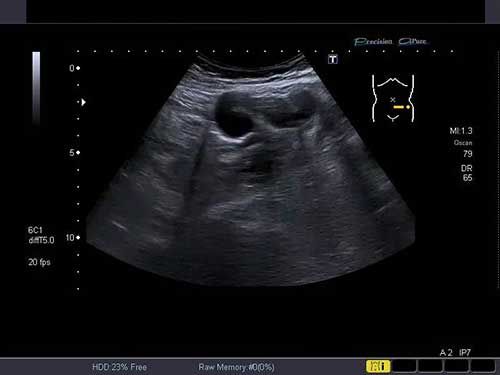

Challenge your diagnostic skills with these images of a pelvic mass.

Challenge your diagnostic skills with these images of the left hemipelvis of a young woman.